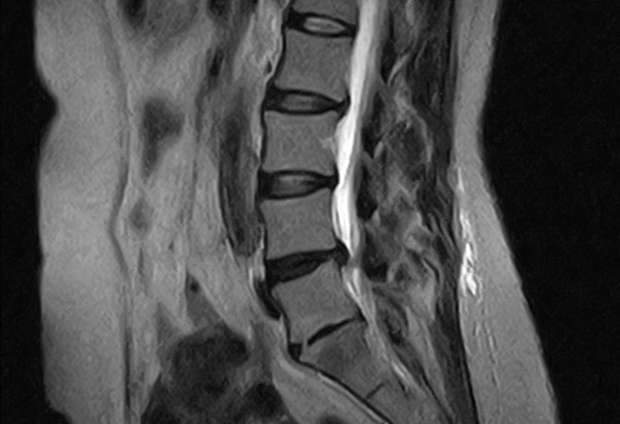

腰椎椎間板ヘルニアの治療について

腰から臀部にかけての痛み、下肢の痺れや痛み、足に力が入りにくいなどの症状のほか、進行すると背骨の変形などがみられる場合もあります。動作が緩慢になる、重い物を持つと痛みが強くなる場合には、「腰椎椎間板ヘルニア」の可能性があります。

背骨でクッションの役割を果たす椎間板の一部が飛び出して、神経を圧迫し痛みなどさまざまな症状が現れます。

• X線検査(レントゲン)やMRI検査を行い、診断します。 ※MRI検査については他院で撮影となります。